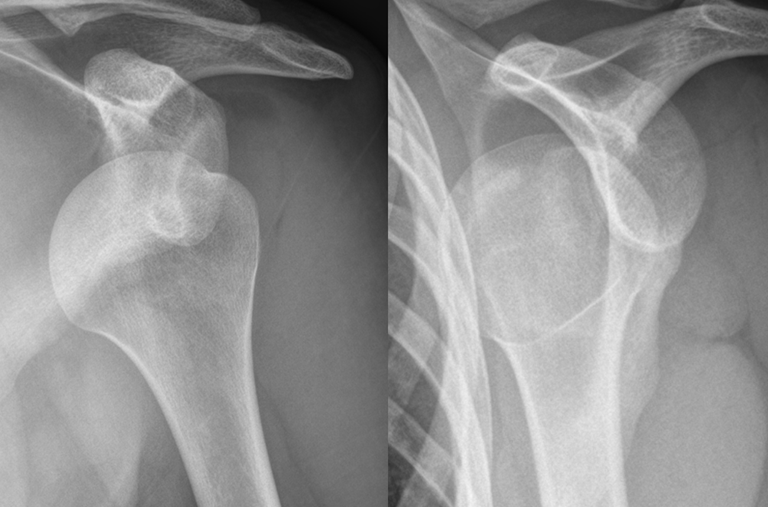

FOR SHOULDER INJURY

An associate at Whiteside & Goldberg, secured a $710,000 settlement on behalf of a 51-year-old man who suffered a significant shoulder injury in a car accident. The man ended up needing invasive surgery to repair the damage to the shoulder, but thankfully, he made a full recovery after physical therapy. While $710,000 is a tremendous amount of compensation for a shoulder injury, it represents the relentless pursuit of Whiteside & Goldberg when working up a case to maximize our clients’ compensation. What is equally impressive is that the associate was able to obtain this fantastic result for his client without ever filing a lawsuit.

FOR FORKLIFT OPERATOR WHO SUFFERED TORN LABRUM

Jason M. Whiteside earned over a $450,000 award for a 51-year-old forklift operator who was in the process of loading materials into a semi-trailer when the trailer pulled forward, causing him and his forklift to fall from the rear of the trailer. The Plaintiff suffered a torn labrum in his left shoulder that required surgery as well as two lower back disc herniations.